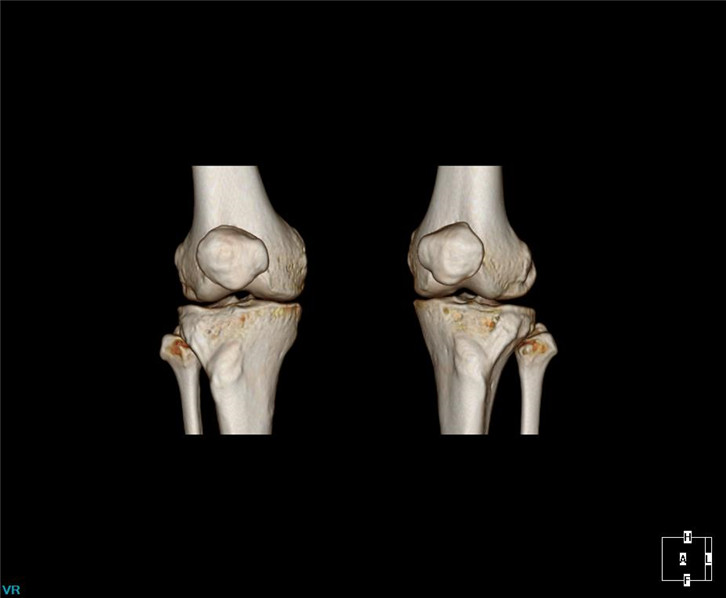

·Comprehensive 32 slices spectral imaging platform enables hospitals at all levels to enjoy the advanced functions of super high-end CT. Spectral imaging platform has rich clinical value in stone composition analysis, gout examination and tumor examination

Clinical Gallery